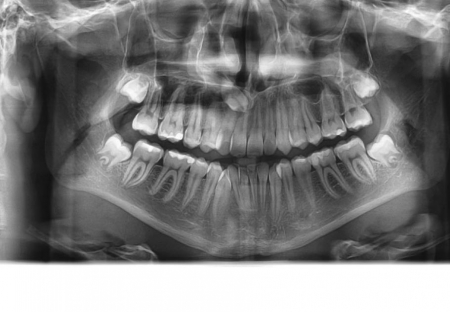

U dolje prikazanim slikama se vidi impaktirani drugi trajni premolar koji je resorbirao dio korijena i krune prvog trajnog molara. Pacijent se javio zbog jakih bolova u području molara koji je bio intaktan te je napravljen ortopantomogram. Molar se morao izvaditi i pacijent je trenutno u terapiji.